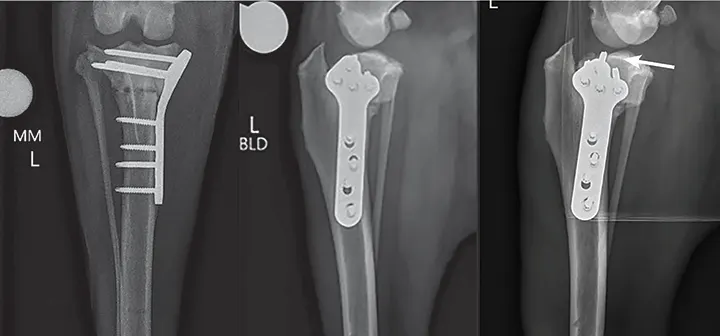

Figure 5

Radiographs from a 5-year-old neutered male Bernese mountain dog with persistent lameness 2 months following TPLO. Radiographs revealed the proximal-most screw violating the joint space (arrow). This is best visualized on the third (oblique) view and was not identified on immediate postoperative radiographs. The locking plate is designed to reduce the risk of intra-articular screw placement, but this plate was contoured intraoperatively to accommodate for excessive medial buttress, which resulted in a screw trajectory directed toward the joint space.